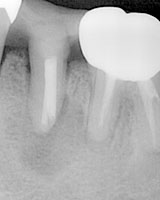

歯根端切除術を行った例です。

向かって左の2本は歯の中にあります白く写る神経の薬の入りが悪く、根の先が黒くなり、骨が溶けているのがわかります。

まず通常の神経の治療を行いました。

これにより右寄りの歯は症状も落ち着き、薬は根の先まで入れ、かぶせ物をしました。

ところが左の歯は赤丸で囲んだように根の先が太く破壊されており、治療をすすめても膿が止まりませんでした。

そこで、根の中に薬を入れ、

歯ぐきに切開を加え、外科的に根の先端を3ミリほど取り除き、根の先端側から薬を追加し糸で縫いました。

術後5か月目の写真です。

以前あった根の先の黒さが薄れ、骨が回復してきているのがわかります。